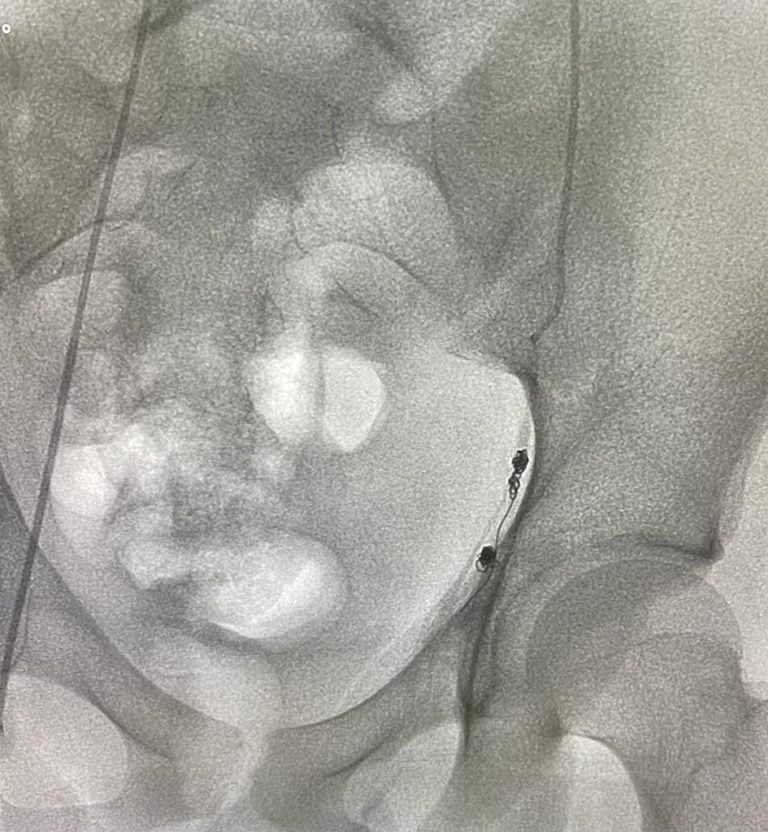

Pelvic congestion syndrome is caused by enlarged pelvic veins that pool blood and trigger ongoing …